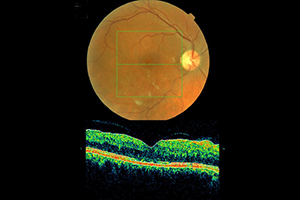

Mit dem Einsatz der optischen Kohärenztomographie (OCT) gelingt es genaue Informationen über die kleinsten Ebenen im Auge in höchster Qualität und Auflösung zu erhalten. Oft kann diese nicht invasive Methode sogar eine fluoreszenzangiografische Untersuchung ersetzen, bei der ein Farbstoff in die Armvene injiziert wird. Bei manchen unklaren Netzhauterkrankungen, bei denen der Befund einen normalen Augenhintergrund und Fluoreszenzangiographie zeigt, kann erst durch die OCT die richtige Diagnose gestellt werden.

Die Untersuchung am OCT ist ähnlich einem Foto ohne Blitz und dauert nur wenige Minuten. Sie erfolgt absolut schmerzfrei und ohne Berührung der Augen. Die Netzhaut wird in dem untersuchten Bereich durch ein Laserverfahren in optische Schnitte zerlegt und es kann damit wie bei einem mikroskopischen Gewebeschnitt die Netzhaut des Auges beurteilt werden. Die Auflösung der erzeugten Bilder ist ca. 10-mal höher als bei herkömmlichen Ultraschallverfahren am Auge und wesentlich genauer als bei einer Computertomographie (CT) oder einer Magnetresonanztomographie (MRT).

Der optische Schnitt einer normalen Netzhaut

Die untere Abbildung zeigt einen Schnitt durch die Netzhautmitte (Makula) mit der wichtigen Stelle für das Scharfsehen - die Sehgrube (Fovea). Die Einsenkung stellt den Normalbefund dar, welches in der dreidimensionalen Bildgebung besonders gut veranschaulicht wird.

normaler Netzhautbefund - OCT

normaler Augenhintergrund

3D Darstellung- OCT

Beispiel: Feuchte altersbedingte Makuladegeneration

68-jähriger Patient mit zunehmender Sehminderung seit 6 Wochen auf 0,3 (30%). Nach 3-maliger Anti-VEGF Therapie Rückgang des Ödems und Besserung auf 0,5

Beispiel: Venöser Gefäßverschluss

58-jähriger Patient mit plötzlicher Sehminderung seit 6 Wochen auf 0,1 (10%). Nach 3-maliger Anti-VEGF Therapie Rückgang des Ödems und Besserung auf 0,63

vor der Behandlung

nach der Behandlung